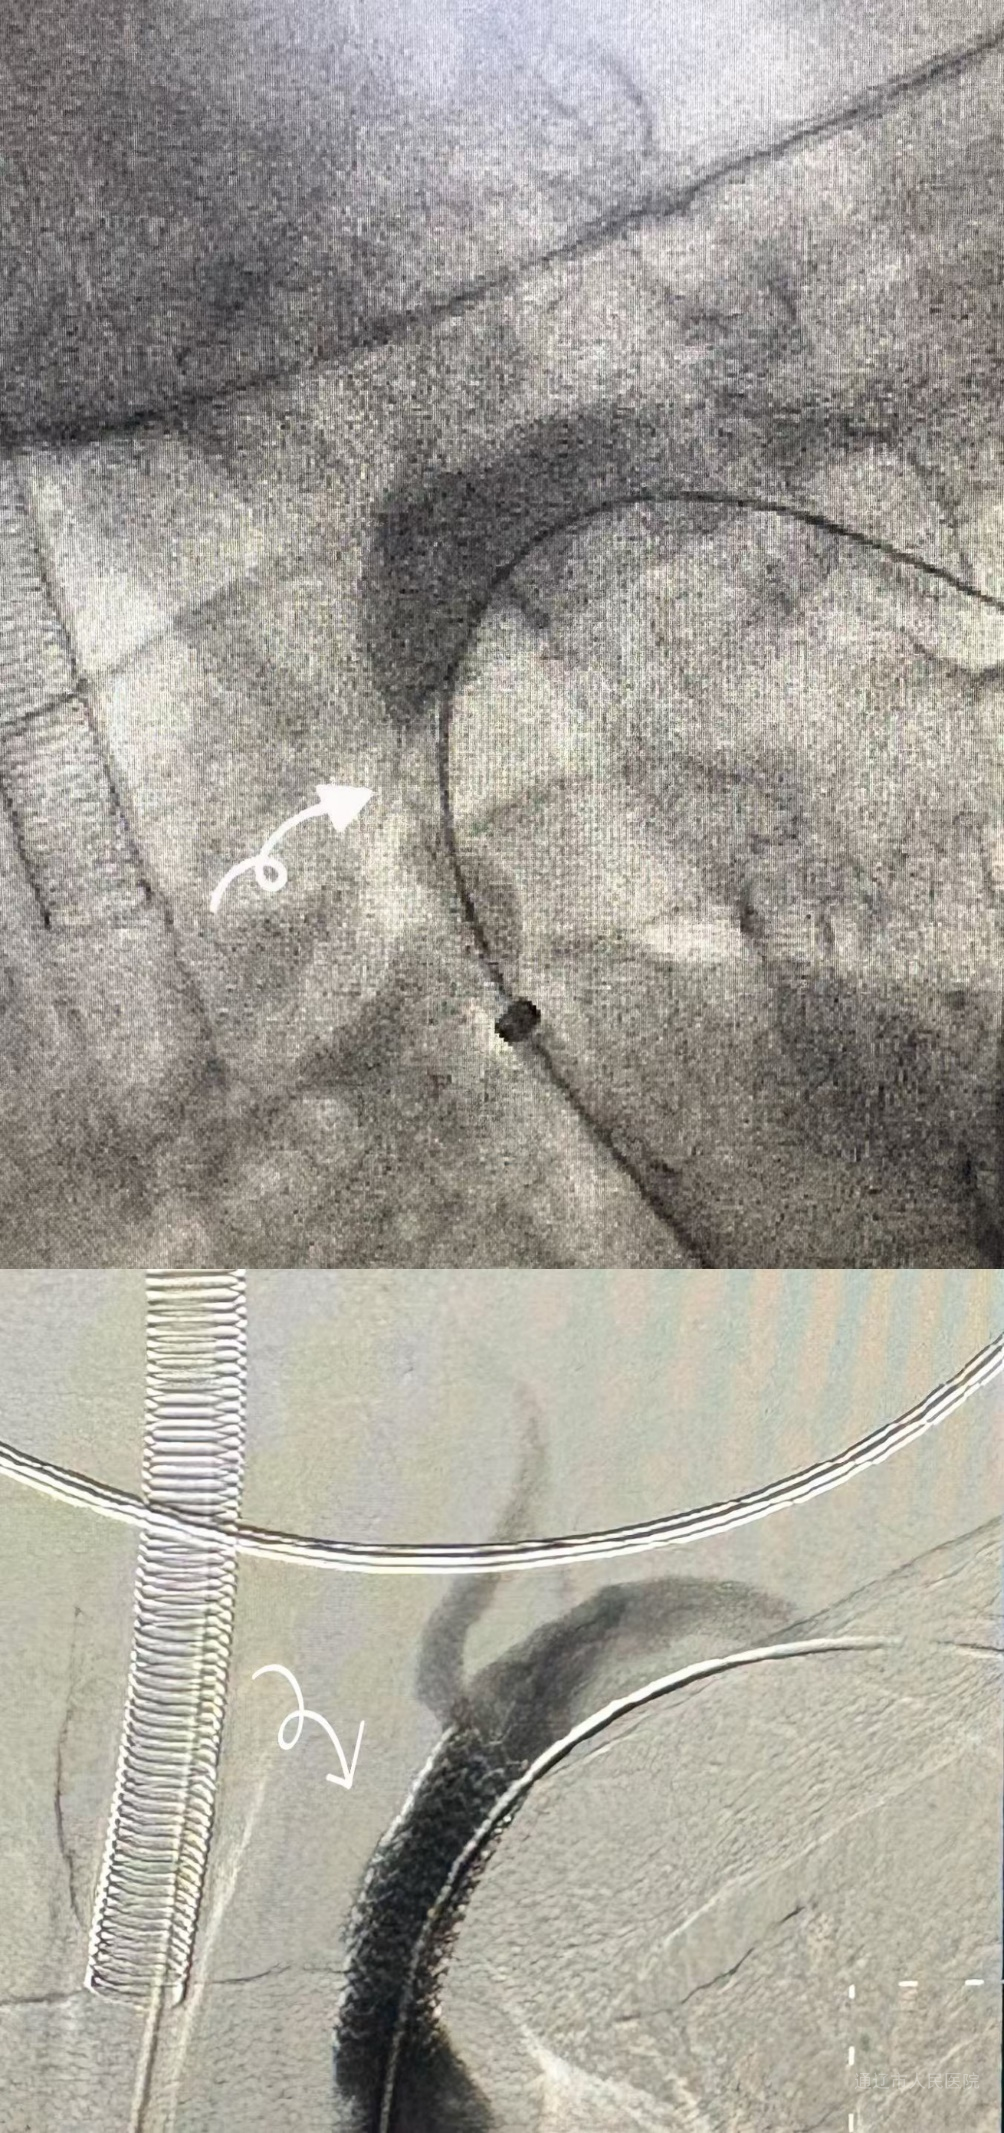

在麻醉科与介入导管室护理团队配合下,手术分阶段推进:心脏血管外科团队先穿刺右侧股动脉,缓慢置入导丝及造影导管,避开主动脉弓溃疡,使用球囊导管预扩左侧锁骨下动脉狭窄处后成功置入左侧锁骨下动脉支架恢复血流,再精准释放胸主动脉覆膜支架隔绝溃疡风险,支架位置良好,无内瘘。随后心血管内三科团队接力,通过同一股动脉入路,运用支架对吻技术、震波球囊、血管内超声的技术,成功实施“冠状动脉支架置入术”,恢复心肌供血。术后患者转入ICU监护,次日病情平稳转回普通病房,在心脏血管外科医护团队精细的围术期管理下,患者恢复良好,顺利出院。